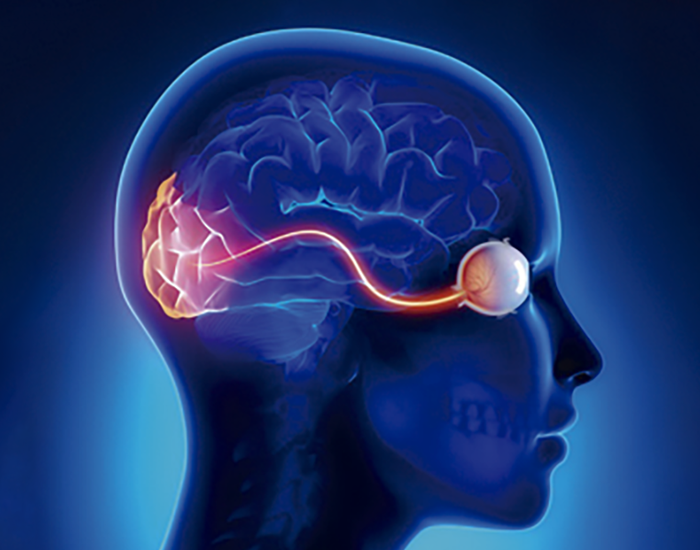

El glaucoma engloba un grupo de enfermedades que provocan un daño progresivo del nervio óptico.

Una de las principales causas de glaucoma es el aumento de la presión intraocular que comprime el nervio óptico, dañándolo poco a poco y de manera irreversible.